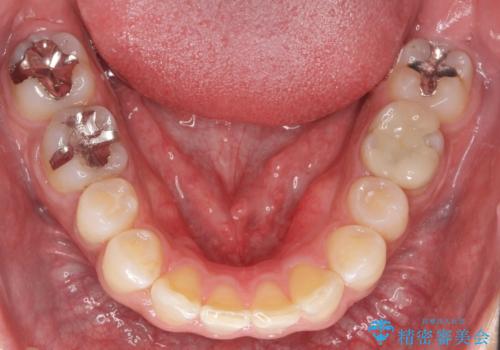

上の前歯が斜めに見えること、犬歯と小臼歯の間の隙間、上下顎前歯のがたつきを治すことをご希望されていました。

気になるのは前歯だけで、奥歯の咬み合わせは気にならないとのことでした。

ご予算と患者様のご希望により、インビザライン・ライト(マウスピース14枚)によるマウスピース矯正を行いました。